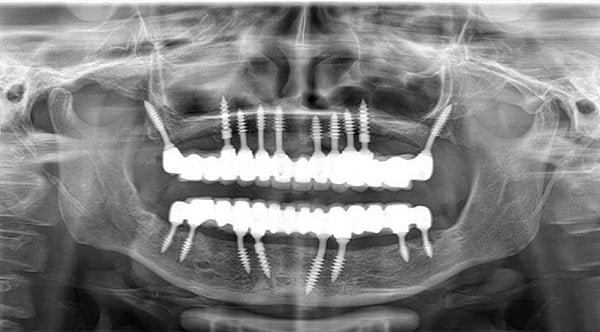

Korticale Basale

Progressive single spiral threads. Higher Bone Implant contact. Improved primary stability. More Resistance to Tensile & Compressive forces. Flame shape threading pattern enables higher primary stability.

Allow insertion in minimum drilling.

Optimum basal bone engagement